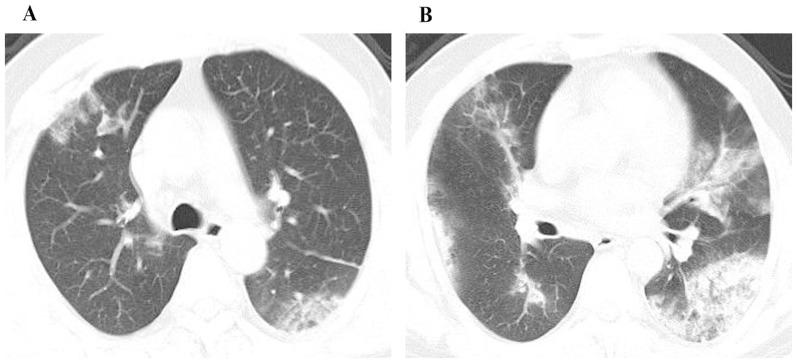

The novel H7N9 virus causes severe illness, including pneumonia and acute respiratory distress syndrome, with high rates of mortality. We investigated the association of initial radiologic characteristics obtained at admission with clinical outcomes in patients with avian influenza H7N9 pneumonia.

Demographics, comorbidities, clinical findings, radiologic appearance and scores of the affected lung parenchyma were compared between survivor group (n = 15) and mortality group (n = 7). Two radiologic scores were calculated, one using chest radiography and one using CT. Follow-up CT scans at discharge were analyzed in 12 patients of the survival group.

All the patients in mortality group developed acute respiratory distress syndrome and required mechanical ventilation, while in the survival group 33% (5/15) developed acute respiratory distress syndrome (P<0.05) and 27% (4/15) required mechanical ventilation (P<0.05). The mean radiographic and CT scores of the mortality group were 50% higher compared to the survival group (P<0.05). ROC analysis revealed an area under curve of 0.738 for the radiographic score with an optimal cutoff value of a score of 19 for prediction of mortality, with a sensitivity of 71% and a specificity of 67%, and an area under curve of 0.833 for the CT score with an optimal cutoff value of a CT score of 21 for prediction of mortality, with a sensitivity of 86% and a specificity of 73%. The mean CT score of the affected lung parenchyma at discharge was 30% lower than the initial CT examination (P<0.05).

High initial radiologic score is associated with mortality in patients with avian influenza H7N9 pneumonia.